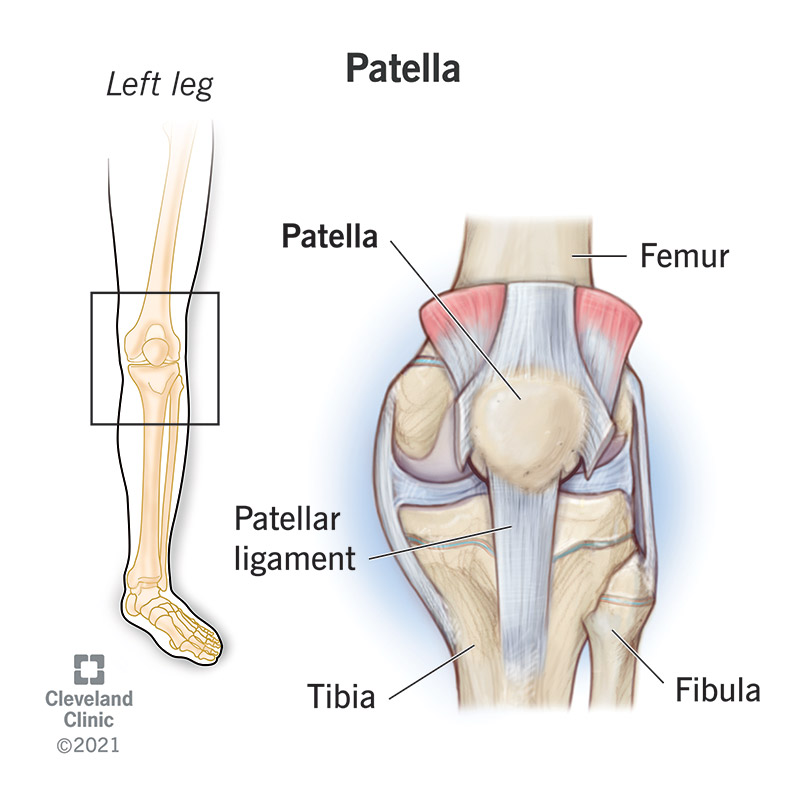

Knee Bones Anatomy Function Injuries Knee Pain Explained shop, Patellar Fractures Broken Kneecap OrthoInfo AAOS shop, Patella Kneecap Anatomy and Function shop, Knee Anatomy Arthritis health shop, The Kneecap Patella and Knee Joint Saint Luke s Health System shop, Patella Wikipedia shop, Knee Joint Function Anatomy shop, Patella the Knee Cap shop, Normal Anatomy of the Knee Joint Middletown Knee Treatment Old shop, Where or Where Has My Patella Gone Direct Orthopedic Care shop, Knee Joint Anatomy and Arthritis SHELBOURNE KNEE CENTER shop, Physiotherapy in Calgary for Knee Pain Bipartite Patella shop, Patella Anatomy function and clinical aspects Kenhub shop, Patellofemoral Pain Syndrome My Family Physio shop, Why You Have a Kneecap and How it Unleashes Your Quads shop, Physiotherapy in Calgary for Knee Pain Bipartite Patella shop, Knee Anatomy Sweep shop, Patella Kneecap Bone Xray Front Anterior Stock Illustration shop, Patella Wikipedia shop, Patella Knee cap Joint surgeon shop, Patella Fracture Broken Knee Cap Orthoriverside shop, Patellofemoral Pain Syndrome OrthoInfo AAOS shop, Knee replacement Understanding your knee shop, Is there something wrong with my kneecap Coastal Orthopedics shop, Has Anyone Dealt With a Knee Cap Bone Spur Training TrainerRoad shop, What You Need to Know About Kneecap Injuries Sports health shop, Knee Trauma Fractures of the Patella Tibial Plateau and Distal shop, Patella or kneecap bone Anatomy bones Leg muscles anatomy shop, Dislocated Kneecap Dislocated Patella for Parents Nemours shop, Kneecap Pain shop, Knee Pain Location Chart SPORT Orthopedics Dallas and Frisco shop, Knee Pain Causes Treatment shop, Why Kneecapping Your Opponent Works shop, Chondromalacia Harvard Health shop, Knee replacement Understanding your knee shop.

Knee Bones Anatomy Function Injuries Knee Pain Explained shop, Patellar Fractures Broken Kneecap OrthoInfo AAOS shop, Patella Kneecap Anatomy and Function shop, Knee Anatomy Arthritis health shop, The Kneecap Patella and Knee Joint Saint Luke s Health System shop, Patella Wikipedia shop, Knee Joint Function Anatomy shop, Patella the Knee Cap shop, Normal Anatomy of the Knee Joint Middletown Knee Treatment Old shop, Where or Where Has My Patella Gone Direct Orthopedic Care shop, Knee Joint Anatomy and Arthritis SHELBOURNE KNEE CENTER shop, Physiotherapy in Calgary for Knee Pain Bipartite Patella shop, Patella Anatomy function and clinical aspects Kenhub shop, Patellofemoral Pain Syndrome My Family Physio shop, Why You Have a Kneecap and How it Unleashes Your Quads shop, Physiotherapy in Calgary for Knee Pain Bipartite Patella shop, Knee Anatomy Sweep shop, Patella Kneecap Bone Xray Front Anterior Stock Illustration shop, Patella Wikipedia shop, Patella Knee cap Joint surgeon shop, Patella Fracture Broken Knee Cap Orthoriverside shop, Patellofemoral Pain Syndrome OrthoInfo AAOS shop, Knee replacement Understanding your knee shop, Is there something wrong with my kneecap Coastal Orthopedics shop, Has Anyone Dealt With a Knee Cap Bone Spur Training TrainerRoad shop, What You Need to Know About Kneecap Injuries Sports health shop, Knee Trauma Fractures of the Patella Tibial Plateau and Distal shop, Patella or kneecap bone Anatomy bones Leg muscles anatomy shop, Dislocated Kneecap Dislocated Patella for Parents Nemours shop, Kneecap Pain shop, Knee Pain Location Chart SPORT Orthopedics Dallas and Frisco shop, Knee Pain Causes Treatment shop, Why Kneecapping Your Opponent Works shop, Chondromalacia Harvard Health shop, Knee replacement Understanding your knee shop.